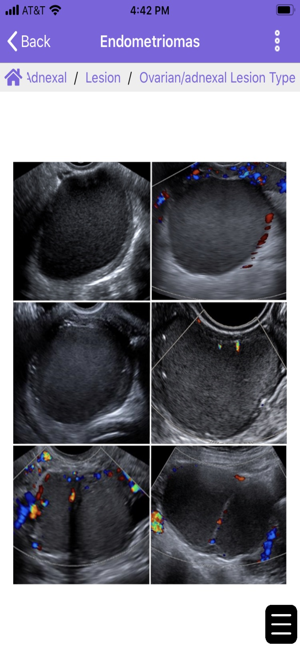

The ACR® Guidance App provides interactive mobile access to select clinical guidance content from the ACR website. Download to access the ACR Contrast Reaction Cards, Reporting and Data Systems (RADS), and Incidental Findings (IF) content. This app is intended for healthcare professionals such as radiologists, oncologists, referring physicians, and medical students who desire on the go reference materials from ACR. This app is not a medical device and should not be considered as one.ACR provides this mobile app for reference purposes only. It is not intended to substitute for the independent clinical judgment of a physician or other health care professional user. A physician or other user is solely responsible for verifying the currency and applicability of app content to a particular clinical situation and thus assumes all risk of use. As allowable under applicable law, ACR and ACR’s employees, officers, directors, agents, contractors and volunteers will not be liable for any damages